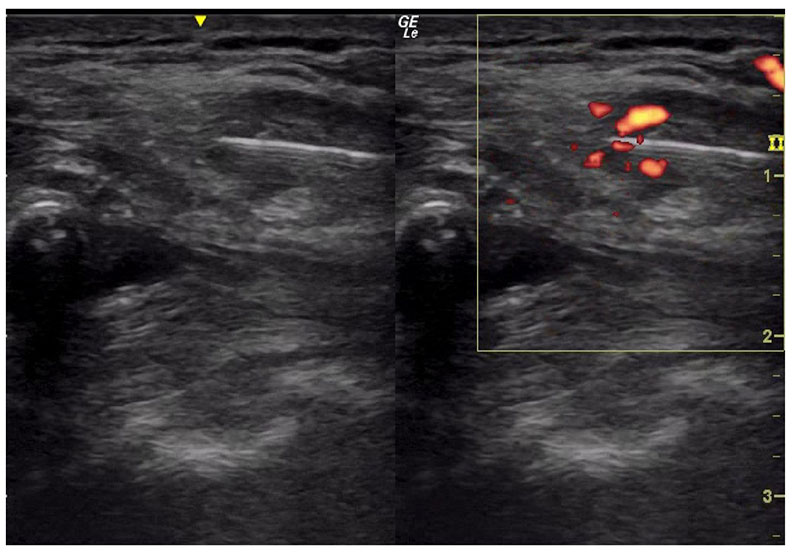

另外如下圖的病人,開完肩峰成形術(acromioplasty),手術後痛到不行,抬也抬不起來。症狀加上位置,我認為也是鎖骨上神經發炎,肌肉骨骼超音波的探頭一放上去該病人疼痛的位置,果不其然!燒燙燙,發炎火熱到不行!

這條鎖骨上神經跨過肩峰鎖骨關節(所以如果它有損傷或退化,都可能夾擠到鎖骨上神經),像個八爪章魚一樣包裹在三角肌上,發炎後章魚吸盤大怒!魔爪捉得緊緊的,讓你抬不起手來!